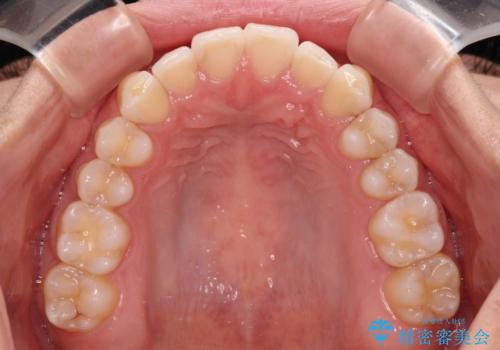

前歯の重なりをインビザライン・モデレートで矯正治療

- 上下前歯の重なりを気にして来院された患者様です。

安価なインビザラインパッケージを用いての治療を希望されており、デコボコの程度が中等度であったため、インビザライン・モデレートを用いて矯正治療を行うこととしました。